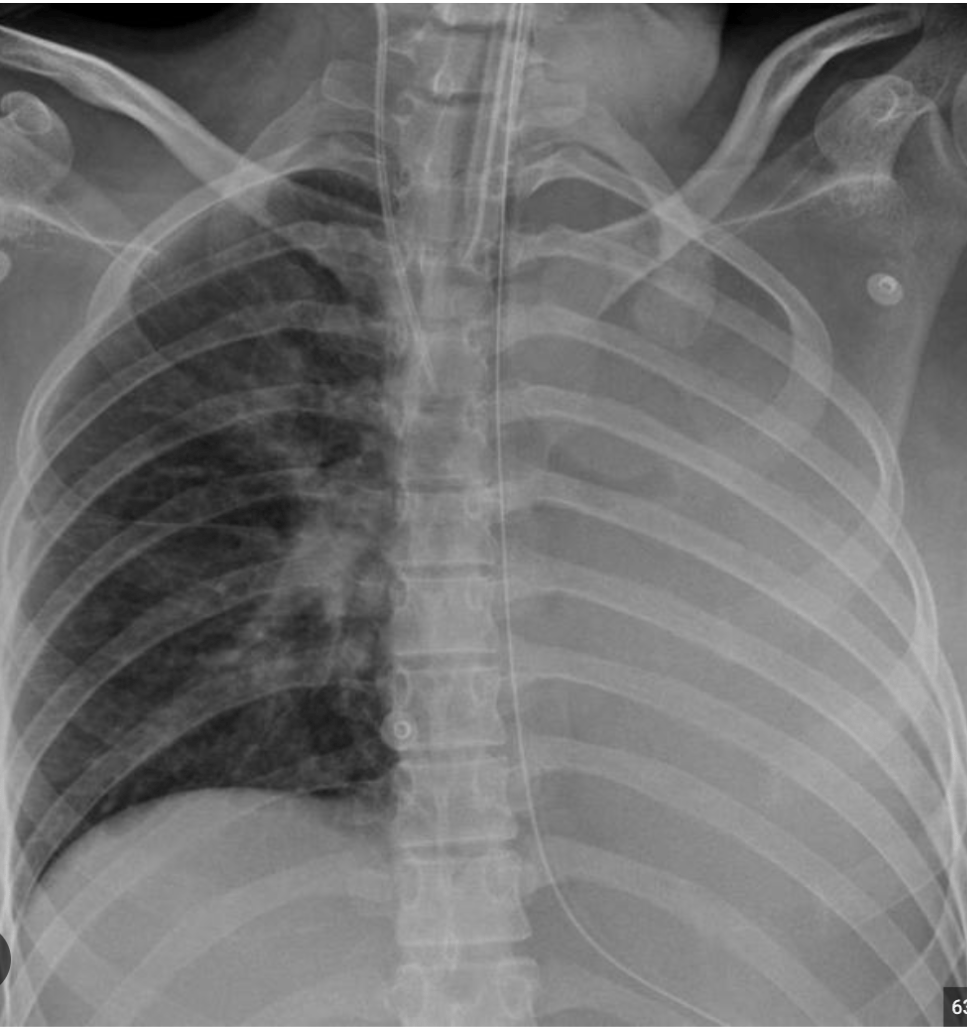

A 81-year-old female with history of atrial fibrillation on Coumadin, hypertension, and recent hip fracture from a fall s/p trochanteric fixation of the femoral head who has been recovering in a skilled nursing facility is brought into the emergency department (ED) with complaints of altered mental status, high fevers, and productive cough. The patient is emergently intubated because of lethargy and is transferred to the ICU. On arrival to the ICU, the patient’ s vitals are HR 110 bpm, BP 90/65 mm Hg, SpO2 91% on 60% FiO2 on the ventilator. ABG is showing pH of 7.38, PaO2 of 88 mm Hg, PaCO2 of 39 mm Hg, and HCO3 of 22. Despite an increase of the FiO2 on the ventilator, increase of PEEP, and repositioning of the ETT, the patient’ s oxygenation does not improve. A decision to obtain a CXR is made and the imaging obtained follows.

What is the next appropriate intervention given these clinical findings?

A. Perform needle decompression of the chest

B. Retract the endotracheal tube by 2 cm

C. Change the patient position from supine to prone

D. Perform a bronchoscopy

E. Insert chest tube on the left side of the chest

Answer: Perform Bronchoscopy (D)

Based on the chest X-ray obtained, the patient’s hypoxemia is due to left lobe collapse. Given the patient’s history of productive cough and purulent sputum, left lower lobe collapse is likely from mucous plugging, and bronchoscopy to clear the mucous plug is advised.

In case of a tension pneumothorax, contralateral shift of the mediastinum, increase in ipsilateral pleural space, and depression of the hemidiaphragm may be observed (Answer A & E Wrong).

Pleural effusion can present similarly to mucous plugging on CXR; however, the key is to look for mediastinal shift. Mucous plugging --> ipsilateral shift / Pleural effusion --> contralateral shift (Answer E Wrong).

Endotracheal tube is in appropriate position --> no evidence for mainstem intubation (Answer B Wrong)

Changing the patient’s position from supine to prone is a technique that can be adopted to improve patient’s oxygenation and V/Q mismatch. It is often employed as an adjunctive measure in patients with severe ARDS (Answer C Wrong).